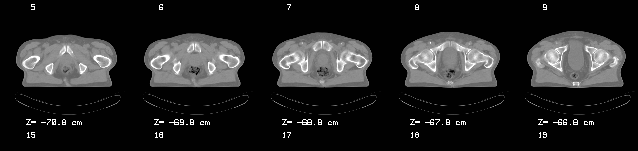

Die zur Planung benötigten CT-Schnitte gelangen über das Netzwerk des Hauses entweder vom Schnittbildzentrum (Somatom Plus 4) oder von der CT-Option des institutseigenen Simulators (Varian Ximatron) in die Planungskonsole. Hier werden die CT-Schnitte kontouriert, damit ist der "Patient" zur Planung bereit.